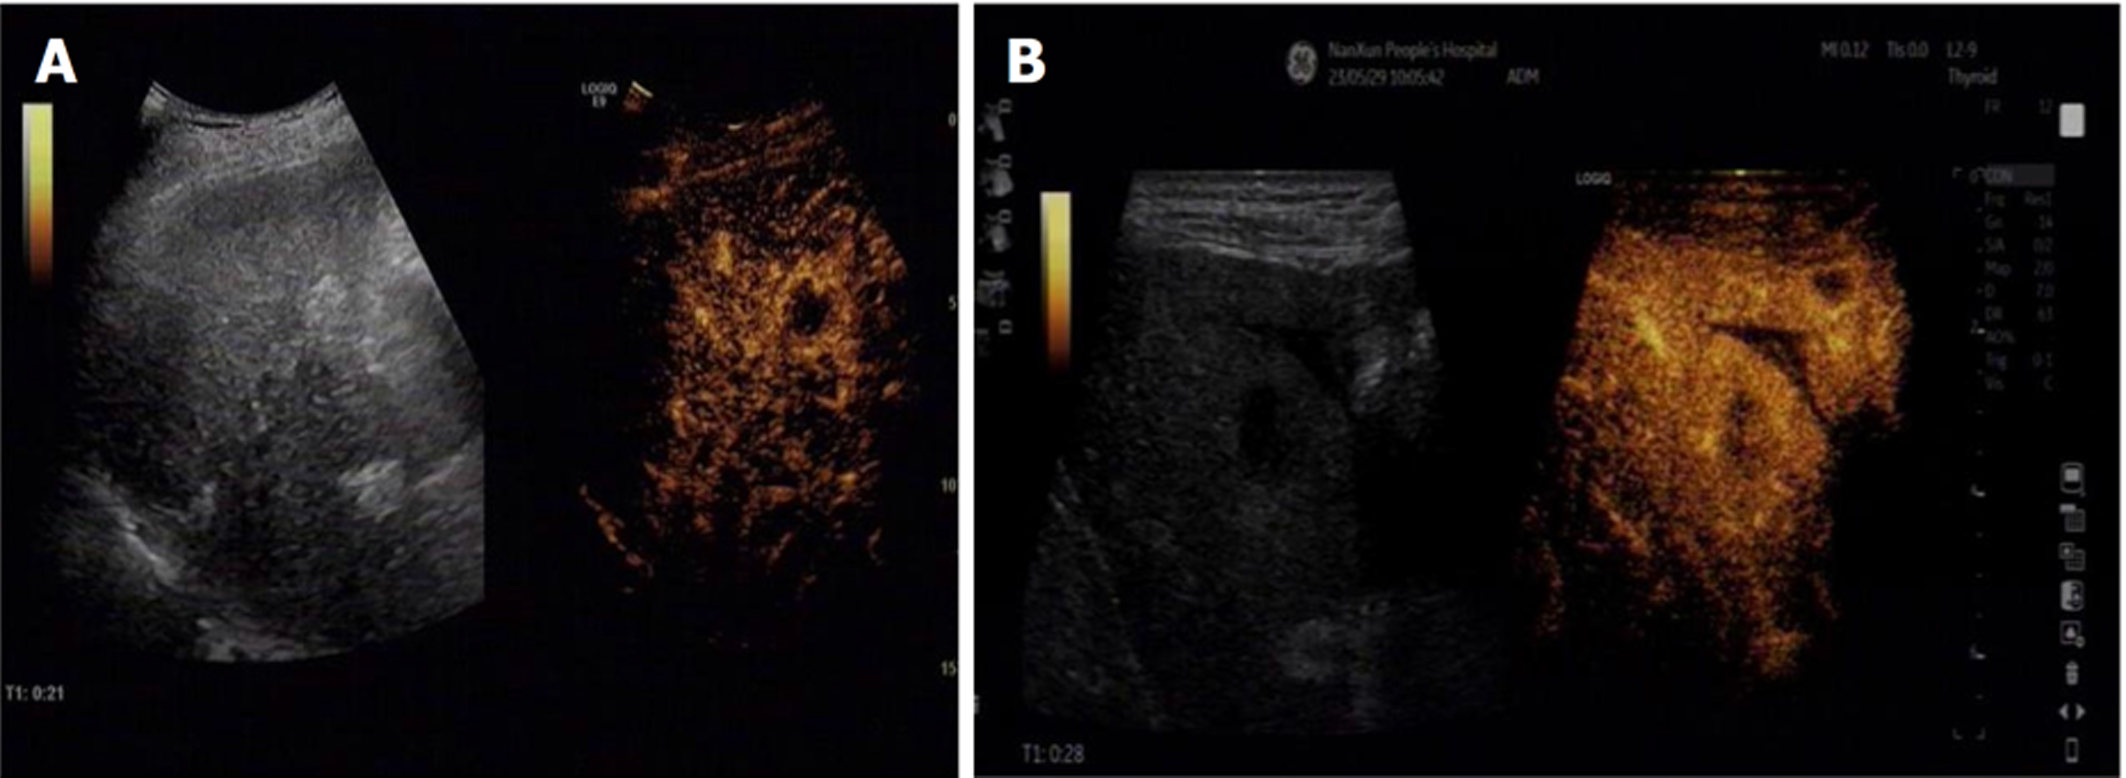

经超声造影检查结果显示, 原发性肝癌动脉相早期呈整体增强, 呈"快进快出"型表现, 边界多不规则, 具有周围血管围绕征, 肿瘤内血流信号杂乱, 肿瘤后方回声无明显变化, 少数后方回声轻度增强; 而肝转移瘤超声造影特征主要呈强回声、不规则形状、快速显影、血供丰富等, 动脉相早期大部分呈整体增强, 周边呈厚圈状增强, 中心部位无增强, 廓清后均呈"黑洞"表现. 见图1和图2.